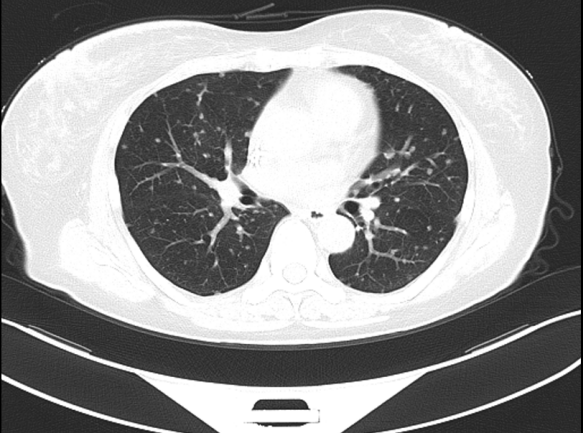

图2. 2019.01两肺转移灶

两个疗程后复查CT:右乳Ca伴右腋下淋巴结M(较前相仿),伴两肺弥漫性转移(图2,较前进展);肝实质异常密度影,考虑转移,较前相仿;胸腰椎转移灶,较前相仿。疗效评价PD。